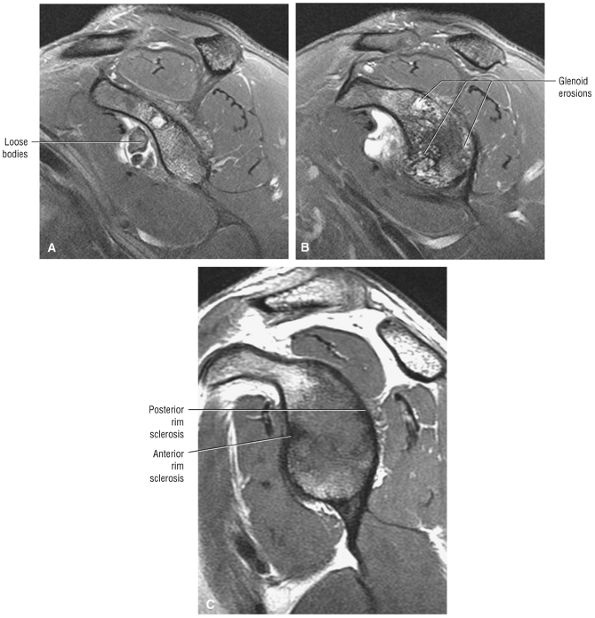

-

Impingement syndrome, a clinical diagnosis, is characterized by a range of MR findings from tendinosis to rotator cuff tears.

Intrinsic impingement is associated with shoulder instability.

Primary extrinsic impingement is associated with abrasion of the rotator cuff against the inferior surface of the acromion.